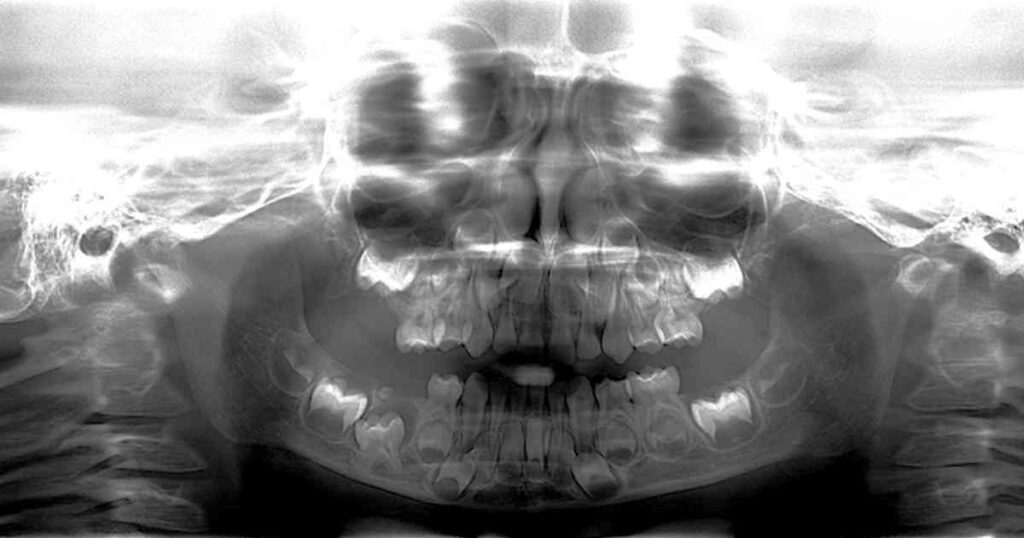

6-year-old boy with lesion at left side of mandible

A 6-year-old boy was brought to the pediatric dentist for an evaluation of a “yellow lesion” at the left side of the mandible, in betwe…

5-year-old girl with a growth on the upper right maxilla

A 5-year-old girl presented to the general dentist because of a “bump” on her upper right maxilla (lingual of tooth #H).